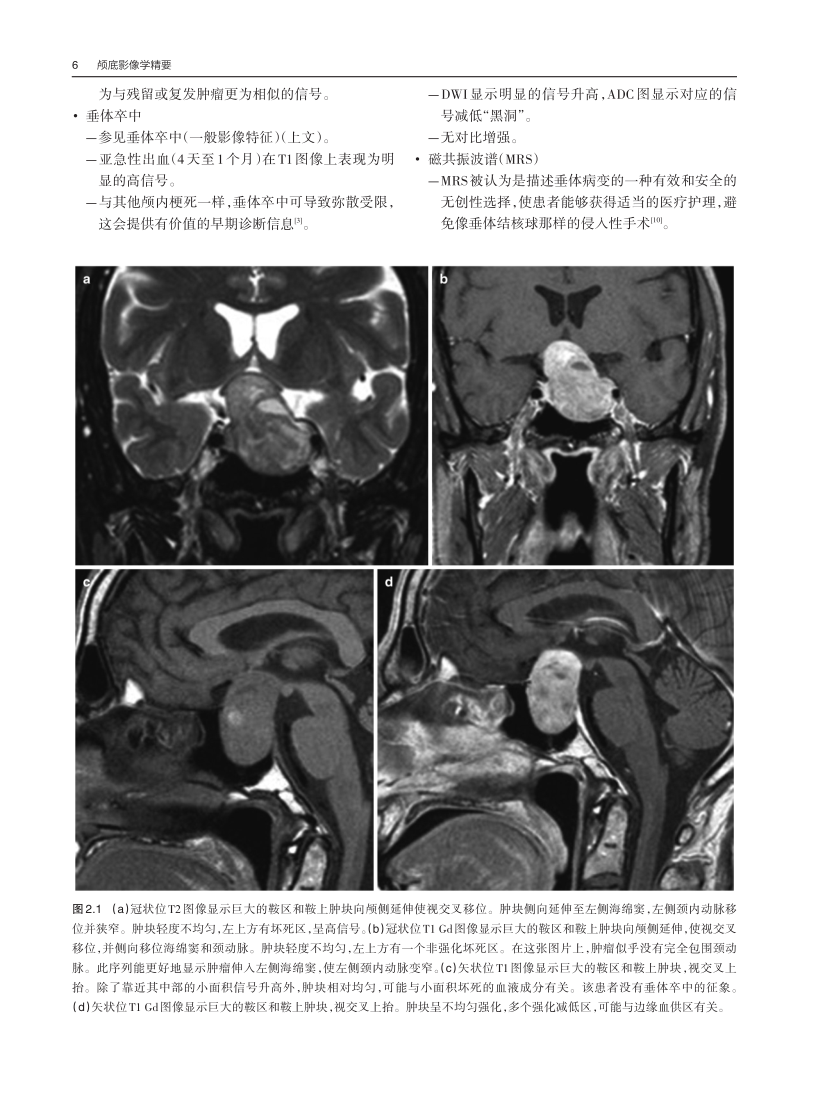

l 配以大量丰富的影像图片,以及部分解剖图片,可以帮助读者更好地掌握颅底解剖结构及颅底疾病的影像特点,便于读者学习。